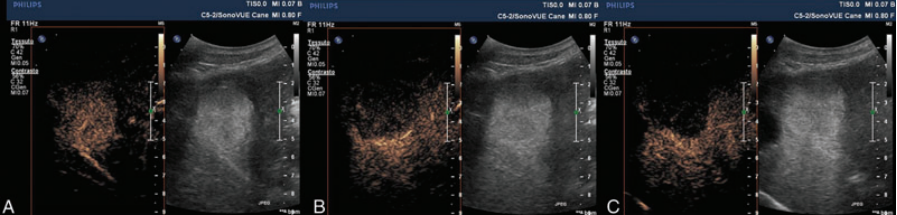

on US you find a hyperechoic liver mass with extra blood supply. A CEUS is performed - images include the arterial, portal and venous phases.

Arterial phase: markedly hyperenhancing (suggesting it has its own blood supply)

Portal and venous phase: hypoechoic to surrounding hepatic parenchyma.

Differentials: benign cholangiocellular adenoma (correct!), and malignant neoplasia - hepatocellular etc.

Imaging diagnosis - Cholangiocellular adenoma: CEUS findings in a benign tumor mimicking malignant neoplasia in a dog. VRU 54.1 (2013).

Using CEUS of a liver mass - what are general benign vs malignant characteristics?

Malignant: hypoechogenicity of lesions compared to normal liver during peak contrast enhancement (due to dual vasculature of the majority of the liver and lack of portal vessels in malignant disease)

Benign: variable phase during arterial phase, isoechoic to surrounding parenchyma in portal/late phases